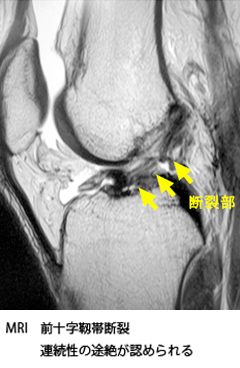

前十字靭帯損傷

前十字靭帯は大腿骨と脛骨(すねの骨)をつないでいる靭帯で脛骨の前方偏位(前への移動)と内旋(内側へのひねり)を制御する役割をしています。